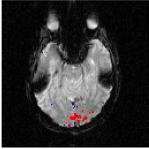

The Experience Based Cognition competition (EBC) (University of Pittsburgh, 2007) offers an opportunity to study complex responses to natural environments. The EBC datasets comprise three 20-minute runs (704 TRs in each run) of subjects interacting in an urban virtual reality environment. Subjects were audibly instructed to complete three search tasks in the environment: looking for weapons (but not tools) taking pictures of people with piercing (but not others), or picking up fruits (but not vegetables). The data was collected with a 3T EPI scanner (TR = s, xy dimension: , voxel size = mm, 34 slices with a thickness of mm). We analyze the second runs of subjects 14 and 13. For each subject, the matrix is composed of intra-cranial voxels at TRs. We first remove the non regionally specific variance captured by the first eigenmodes of a singular value decomposition of the dataset. We then compute using and . After embedding the dataset into four dimensions, we cluster the voxels. Figs. 18 and 20 display the datasets after embedding. Because we cannot display four dimensions, we show the projections of the dataset on three consecutive coordinates. All the coordinates contribute to the spread the dataset along elongated arms, which facilitates the clustering. Voxels that do not correspond to the background activity (the maroon cluster in Figs. 18 and 20) are superimposed on anatomically registered structural images and colored according to their cluster label (see Figs. 19 and 21). For both subjects, the clusters are connected regions (see Figs. 19 and 21), compactly organized around functional areas related to the processing of visual, and auditory stimuli (music, cellphone ringing, dog roaring) in the virtual environment. It is important to emphasize that our method never enforces any form of spatial proximity, and is purely based on functional connectivity.

For subject 14 (Fig. 19), the orange cluster corresponds to activation in the calcarine cortex associated with V1/V2 representations of the lower visual fields, while the light blue cluster corresponds to representations of the upper visual fields. Activation in lateral areas (visual motion areas, MT/V5) is also present, as well as activity in the posterior convexial cortex (area VP). The activation is predominantly in the right hemisphere. Interestingly, the two clusters located in the visual cortex (light blue and orange) have very similar and coordinates (see Fig. 18-left). The cyan cluster corresponds to activation in the right frontal gyrus (Broca area) associated with language comprehension. The yellow clusters are located in the right and left superior temporal gyri and medial temporal gyri (Wernicke area). These regions correlate with activation

in the auditory cortex and language areas. Finally, the dark blue cluster corresponds to activation in the prefrontal cortex. A very similar pattern of activity (Fig. 21) was obtained for subject 13. The blue and orange clusters, located in the calcarine cortex, correspond to V1 and V2 areas. Again, these two clusters, both located in the visual cortex, have similar and coordinates. The green cluster is located in the medial temporal gyrus (Wernicke area) and is associated with language processing.